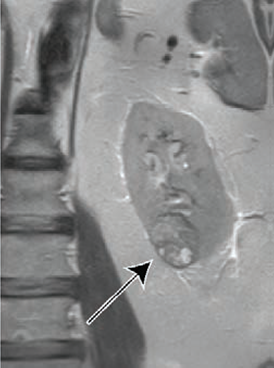

The clear cell likelihood score can help providers determine the growth rate of masses that could be cancerous.